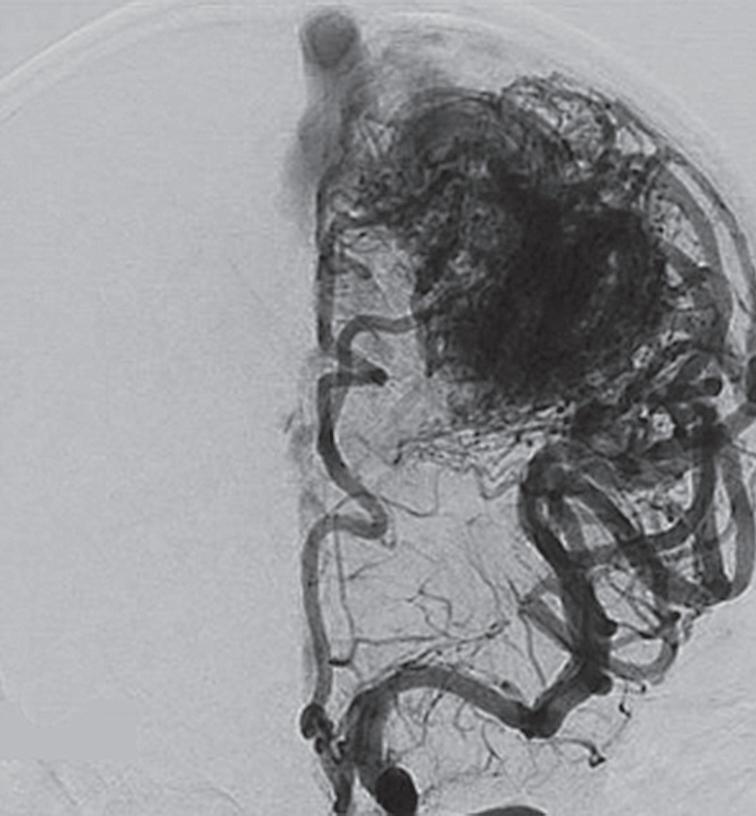

Fig. 1-15. RNM encéfalo T1 (a) sagital sem contraste e (b) axial com contraste demonstrando MAV grau 3, parcialmente embolizada, localizada no giro temporal superior e lobo parietal direito. (c) Arteriografia cerebral em perfil, demonstrando a irrigação pelos ramos da artéria cerebral média e posterior, com drenagem superficial nas veias de Labbé até o seio sigmoide, e o complexo de Trolard no seio sagital superior. O nidus da MAV está demonstrado pelas setas azuis grandes e a drenagem venosa pelas pontas de setas.